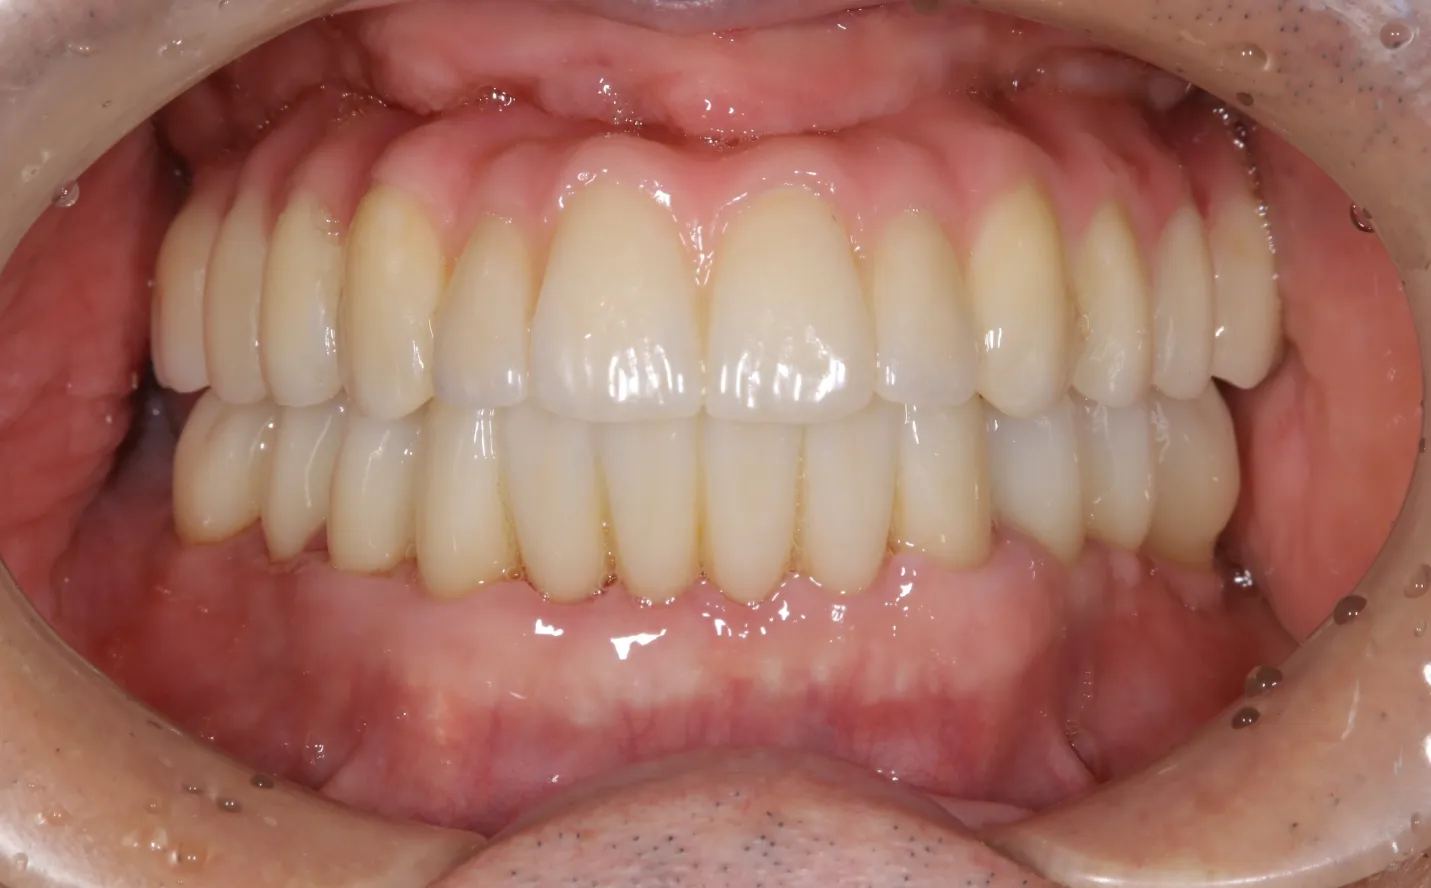

【症例1】

主訴

噛めない。不自由なく食事をしたい。

年齢・性別

50代男性

治療内容

上下顎フルインプラント

期間

1年2ヶ月

費用

7,279,000円